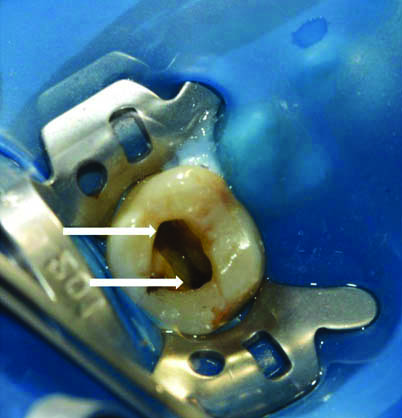

Clinical examination of the pulp chamber floor revealed the presence of only two canal orifices which was further assessed and confirmed with the aid of 3.2x magnification using dental loupes (Admetec Solutions Ltd., Haifa, Israel) with fibreoptic light source that permitted magnification. One orifice was located toward the buccal aspect and was larger in diameter when compared to the typically found buccal orifice in a maxillary first molar. The second orifice was located towards the palatal aspect [Table/Fig-3]. Further close inspection and exploration of the pulpal floor was done for search of additional orifices with the aid of DG-16 explorer under magnification. Additionally, the dentinal map pattern also suggested the presence of two canals.

Pulp chamber floor revealing two large orifices, buccal and palatal.